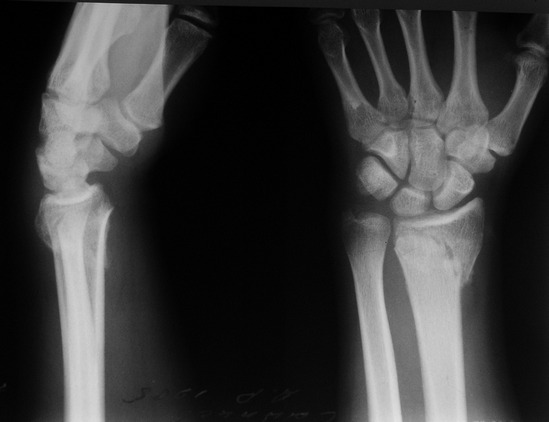

Пациент 23 лет, травма 6 недель назад. В течение всего этого периода проводилась гипсовая иммобилизация.

Patient 23 years old with fracture of the distal radius, managed nonoperatively for 6 weeks.

May this displacement be neglected taking into account the time passed after trauma and X-ray evidence of consolidation?

In this case of nascent or impending malunion in young man 6 weeks after injury where the radiocarpal joint is spared and only the distal radioulnar joint is involved I will start with mobilization and follow the patient. A word of caution: on AP view S-L joint is widened. Lateral view done in flexion does not permit judgment about carpal stability. Further studies including noninjured wrist are recommended.